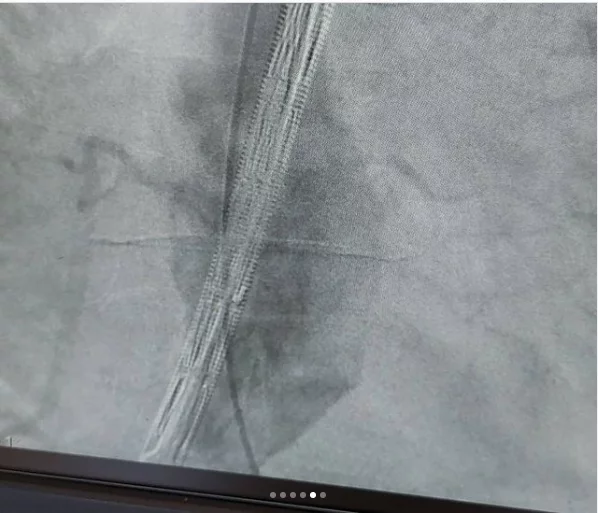

این بیماران با احساس ضربانات مداوم در شکم و درد و گاهاً بدون علامت در معرض خطر پارگی رگ اصلی بدن به نام آئورت ومرگ ناگهانی هستند .دیروز در کمتر از یکساعت بدون جراحی ، استنت هایی که پوشش دیواره ای دارند را مثل لوله داخل ناحیه آنوریسم/یا گشاد شده، تعبیه کردیم و آئورت به سایز نرمال برگشت.